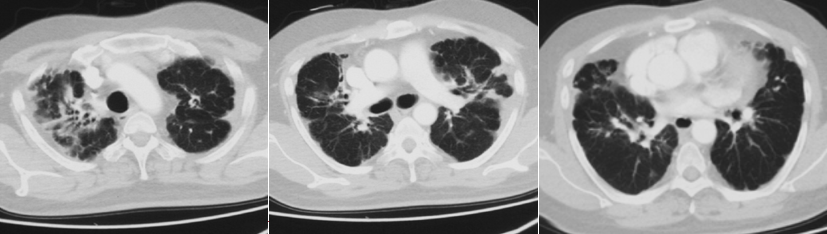

第1次住院(2018年1月8-21日):2018年1月,患者无明显诱因出现咳嗽、咳少量白痰,伴剧烈活动后气短,闻刺激性气味或冷空气咳嗽加重,于当地县医院住院。1月19日完善胸部CT,诊断为“急性支气管炎,支气管扩张”,于1月8-21日予哌拉西林他唑巴坦3.375 g qd+左氧氟沙星0.4 g qd抗感染治疗2周,症状减轻出院,仍间断咳嗽、剧烈活动后气短,冬季感冒后加重。1月19日胸部CT:双肺各叶散在分布斑片样高密度影,密度不均,边界模糊,双肺上叶病灶可见支气管充气征,双侧胸膜局限性增厚(图1)。

第2次住院(2020年10月30日-11月12日):2020年10月18日“着凉”后再次咳嗽、气短加重,伴少量白痰,伴右侧胸痛,慢走200 m感气短,重体力活时可自闻及喘鸣音。当地门诊给予“头孢哌酮他唑巴坦、左氧氟沙星”静滴抗感染12 d,效果差,再次于沧县医院住院。血常规:WBC 13.23×109/L(↑),NEU 10.65×109/L(↑),LYM 1.7×109/L,血红蛋白156 g/L,血小板491×109/L。血气分析(吸氧条件不详):pH 7.422,PaO2 66.5 mmHg(↓),PaCO2 46 mmHg(↑),HCO3- 29.9 mmol/L(↑),BE 5.4 mmol/L,Lac 2.1 mmol/L。血沉 6.6 mm/h。痰细菌培养结果为粪产碱杆菌。超声心动图:左房内径31 mm,左室内径42 mm,右房内径38 mm,右室内径36 mm,主肺动脉19 mm,射血分数(EF)56%。三尖瓣少量反流,左室舒张功能减低。10月30日胸部CT:右肺上叶支气管旁斑片影,较2018年1月19日增多,左上肺新发斑片影、结节影,双肺胸膜增厚,较前加重(图2)。

11月10日(激素治疗12 d)复查胸部CT:双肺斑片影、结节影、磨玻璃影较前吸收(图4)。